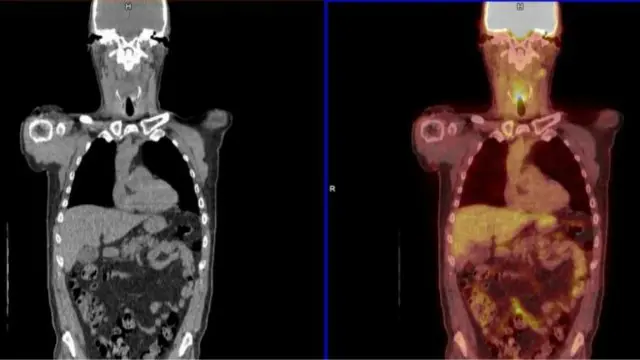

اسکن پیایتی-سیتی (PET-CT) از یک نوع به اصطلاح رنگ پرتوافشان که جذب سلول های سرطانی می شود استفاده می کند.

این به پزشکان اجازه می دهد ببینند آیا سرطان های سر و گردن هنوز فعال هستند یا نه.

پروفسور حشام مهانا، از دانشگاه بیرمنگام، به بی بی سی گفت: "سلول های سرطانی در میان سلول های مرده پنهان می شوند، و با اسکن پیایتی-سیتی می توانید آنها را شناسایی کنید و دریابید که هنوز زنده هستند یا نه."